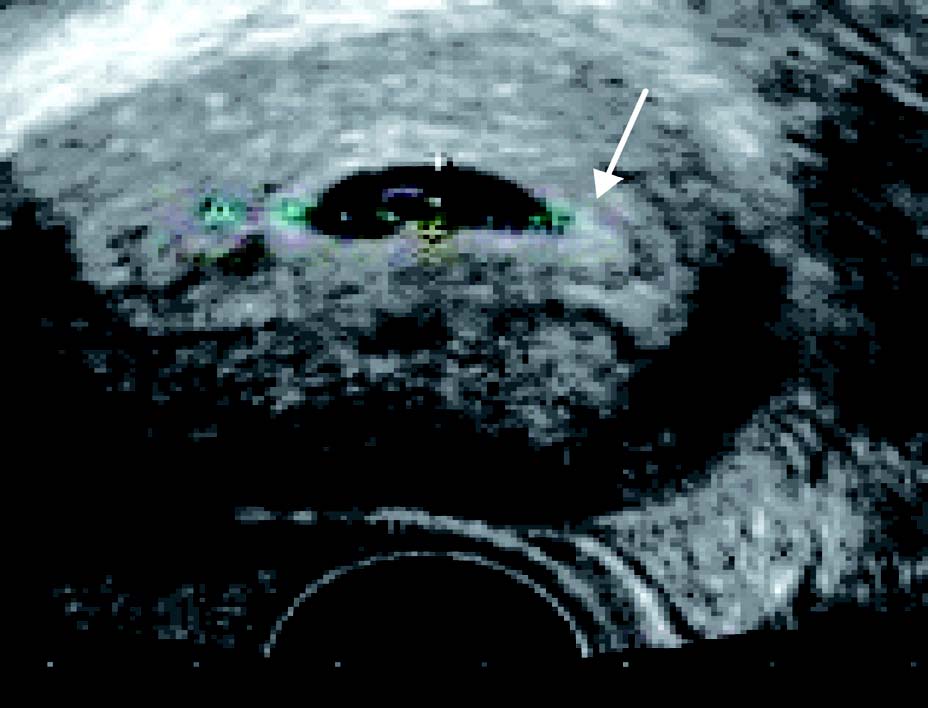

患者25 岁。停经35 天,尿HCG(+)。经阴道超声后位子宫纵切面:宫腔内见偏于一侧内膜的圆形囊性结构为胚囊(GS),称偏心圆;囊壁规则,呈中高回声,内部无回声;胚囊前后径2.7 mm;经阴道超声后位子宫横切面:测得胚囊横径为3.0 mm

超声诊断:宫内早早孕。